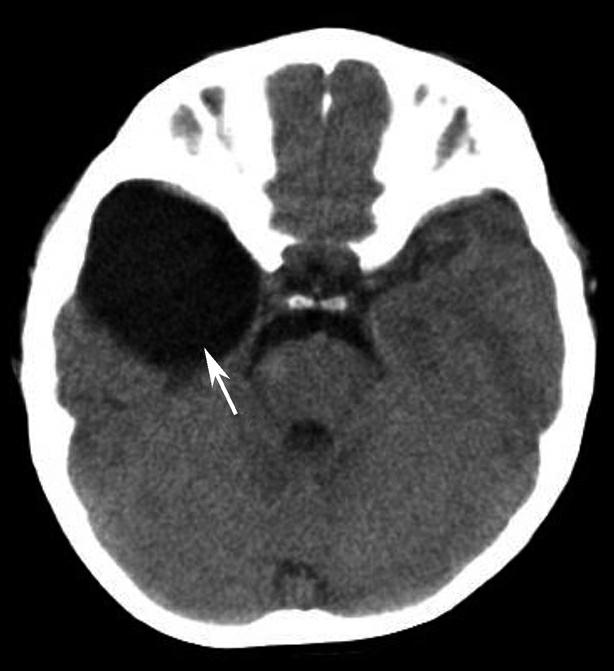

破裂孔、卵圆孔、棘孔及斜坡等均为重要的解剖结构,临床常见疾病如鼻咽癌常侵犯上述结构(图1-2-3)。颈静脉孔区较常见的肿瘤为颈静脉球瘤,常伴有颈静脉孔及其邻近骨质的破坏(图1-2-4)。

图1-2-3 鼻咽癌颅底骨质破坏

A.横断面;B.横断面(骨窗)

骨窗示左侧岩尖、斜坡、左侧蝶骨大翼骨质破坏、受侵(白箭),肿瘤经破裂孔侵入颅内(黑箭头)